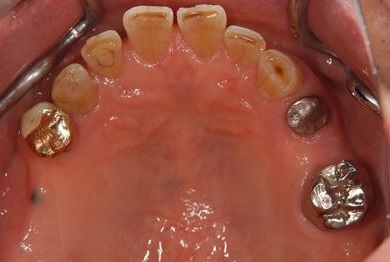

セラミックの症例写真 SHINBI

抜歯即日スピードインプラント治療+歯周外科治療

| 性別/年齢 | 男性 / 62歳 | ||||||||||||||||||||||||||||||||

| 主訴 | 左下の奥歯のブリッジがゆれて、痛みがある。 | ||||||||||||||||||||||||||||||||

| 治療方針 | 抜歯と同時にインプラント埋入を行い、治療期間を短縮する。 | ||||||||||||||||||||||||||||||||

| 治療内容 | インプラント2本(抜歯即日スピードインプラント)、ハイブリッドセラミッククラウン2本、歯周外科治療 | ||||||||||||||||||||||||||||||||

| 総治療費 | 771,960円 | ||||||||||||||||||||||||||||||||

| 治療期間 | 6ヶ月 |